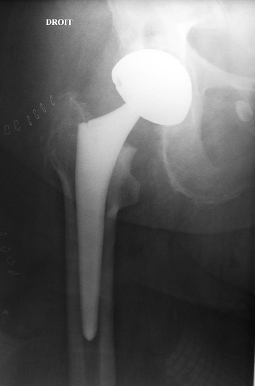

Mme P. née en 1929 a été opérée sans problème d’une prothèse de hanche droite pour coxarthrose. Les radiographies postopératoires immédiates sont parfaites.

Deux mois après, elle ressent une douleur de la cuisse au niveau de la queue de la prothèse, elle continue l’appui qui est de plus en plus douloureux.

La radiographie du 13 février montre la fissure diaphysaire (flèche rouge) et un descellement de la prothèse (flèche bleue).